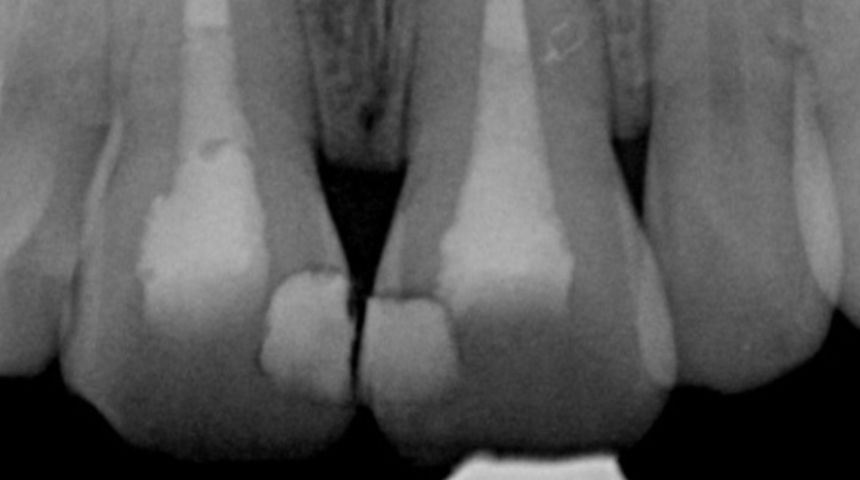

Take a look at some of our recent cases below!